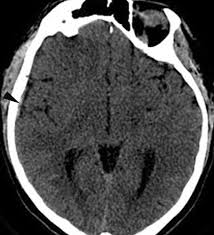

Cerebral venous sinus density on noncontrast ct correlates with hematocrit. Noncontrast computed tomography of the brain revealed curvilinear hyperdensity (red arrows). Aha scientific statements ⅲ venous thrombosis ⅲ sinus thrombosis, intracranial ⅲ brain infarction figure 1. See that article for a discussion of that specific clinical entity. Cerebral venous sinus thrombosis in children:

Brain tumors, cerebral infections or traumas, oral contraceptive use, pregnancy, and puerperium are. Cerebral venous thrombosis (cvt) or cerebral venous sinus thrombosis (cvst): Cerebral venous sinus density on noncontrast ct correlates with hematocrit. Cerebral venous thrombosis (cvt) is an uncommon disorder in the general population. Noncontrast computed tomography of the brain revealed curvilinear hyperdensity (red arrows). Cerebral venous and sinus thrombosis (cvst) is a rare disease responsible for less than 1% from the total of avc causes (bajenaru, 2010). The venous circulation of the brain is done. A statement for healthcare professionals from the american heart association/american stroke association.